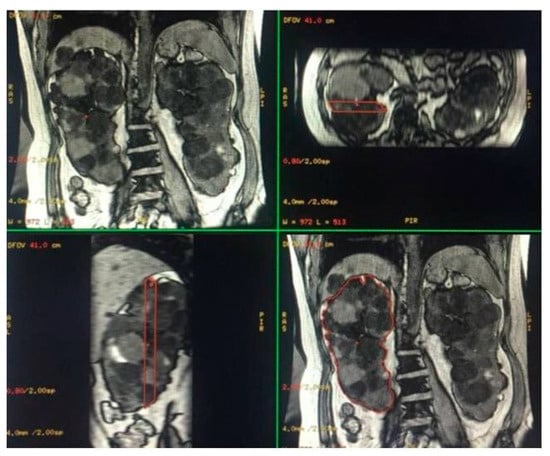

SSFP and SSFSE acquisition planes were used for the evaluation of kidney volume through the ellipsoid method (Figure 1). The diameters of kidneys were measured in millimetres, and the online calculator tool developed by the Mayo Clinic and freely available on the Mayo website [14,18] was used to calculate the SKV and the TKV. For patients with only one native kidney, TKV coincided with the volume of the single kidney. Volumetric segmentation (Figure 2 and Figure 3) was performed using a dedicated workstation (Advantage Workstation 4.6 General Electric; GE Healthcare, Milwaukee, WI, USA).

Figure 1.

MRI measurement of renal diameters on the right kidney of a patient with ADPKD for SKV computation using the ellipsoid method. Coronal length (A), sagittal length (B), width and depth (C).